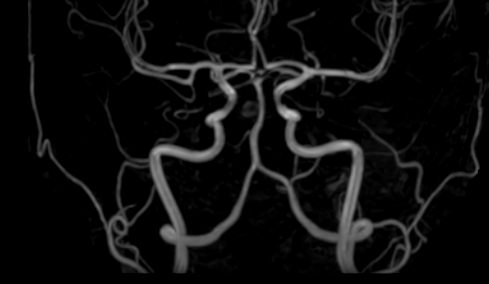

Исследования выполняются на современном высокопольном томографе экспертного класса TOSHIBA VANTAGE TITAN 1,5 Тесла, который использует разные режимы сканирования с толщиной среза от 1мм в различных плоскостях с последующей цифровой обработкой полученных данных для создания трехмерных изображений. МР-ангиография отображает состояние артериальной системы кровоснабжения головного мозга. МР-венография головного мозга позволяет детально изучить особенности венозного русла головного мозга.

Компьютерная программа обрабатывает данные, полученные при сканировании, и формирует объемные изображения как самого мозга, так и сосудистой системы в отдельности без прилегающих тканей. Методики применяются одновременно и взаимодополняют друг друга.

• патология нервов на фоне сосудистых проблем (вазоневральный конфликт — сдавление нерва близлежащим сосудом, также на фоне патологической извитости, аневризмы, сосудистой мальформации).